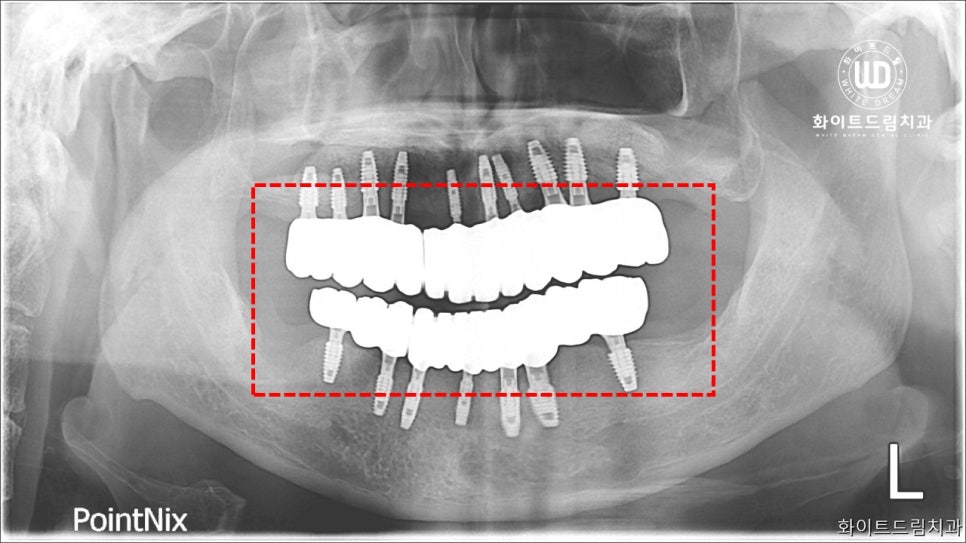

단순 보철 식립이 아닌 기존에 남아있던 치아들이 자라난 방향과 저작상태를 감안하여 임플란트 나사를 식립했습니다. 전체임플란트 사례이나, 고령의 나이이신 점을 감안하여 전반적인 건강상태에 무리가 가지 않도록 상악부터 소량의 임플란트보철을 먼저 식립했습니다.

전체 치아를 발치하여 임플란트를 진행하는 것에 대해 걱정이 많으신 환자분이었던 만큼 임플란트 식립 과정에서 지지기능을 튼튼하게 해드리기 위해 치조골 이식술을 동반해드렸습니다.

2주 간격으로 3번에 걸쳐 상악동 거상술과 치조골이식술을 진행하여 뼈가 퇴축하는 것을 방지하고, 심미적으로도 악안면 구조를 재편할 수 있도록 도와드렸습니다. 그리고 5개월 후 임플란트 보철을 올려 마무리 진행을 도와드렸습니다.

치료가 완료된 사진을 살펴보면 임플란트가 뿌리부터 머리까지 나란히 매끄럽게 연결되어 있는 것을 확인하실 수 있는데, 상악 하악의 U자 형태가 본 케이스와 같이 나올 수 있으려면 임플란트 보철 식립 방향을 잘 체크해야합니다.